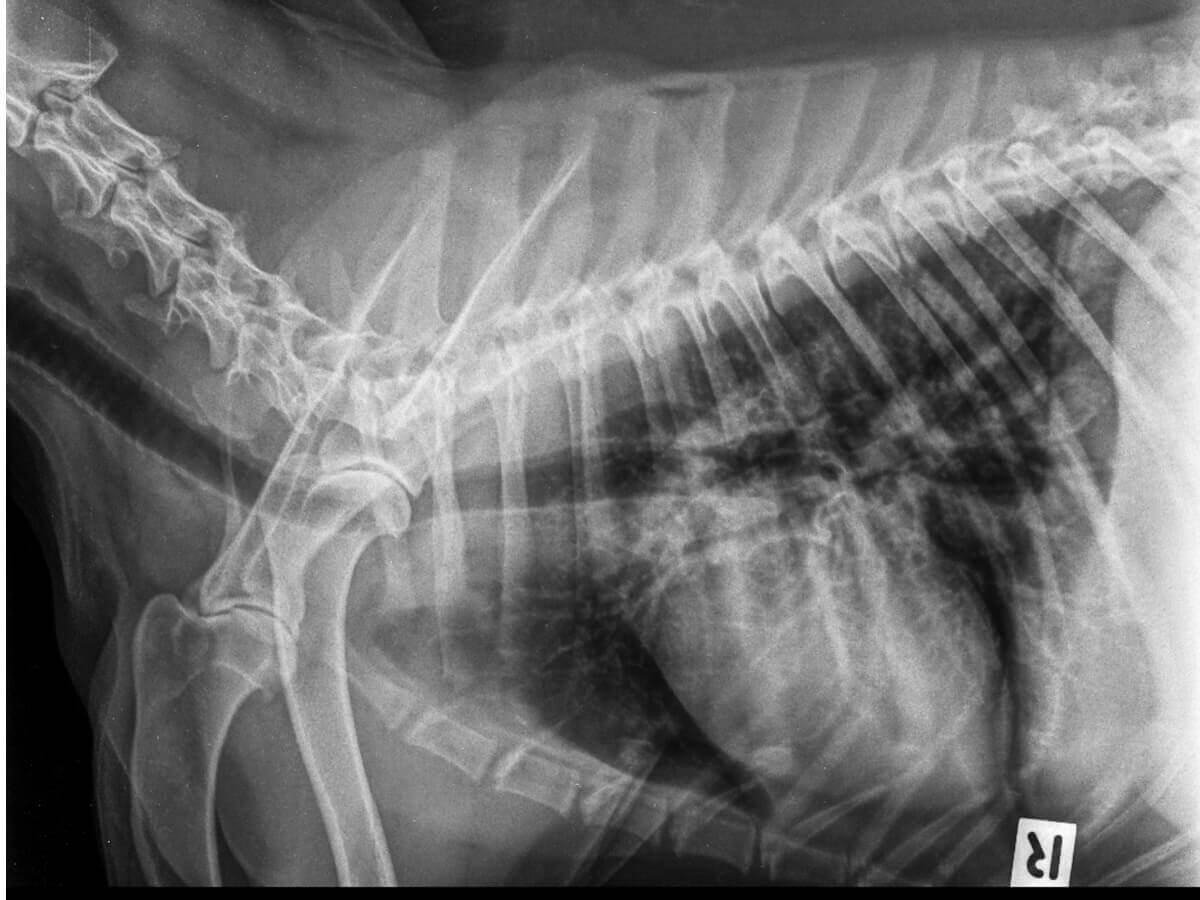

Placas radiográficas

O uso da radiologia permite que a presença de ar seja observada além dos pulmões. É considerado um exame preciso para o diagnóstico de pneumotórax em cães, mas não para identificar sua causa.

Recomenda-se realizar o exame em três projeções, pois isso permitirá visualizar todas as anormalidades nas estruturas dentro da cavidade torácica. Deve ser feito um manuseio cuidadoso para evitar o aumento do estresse do paciente.